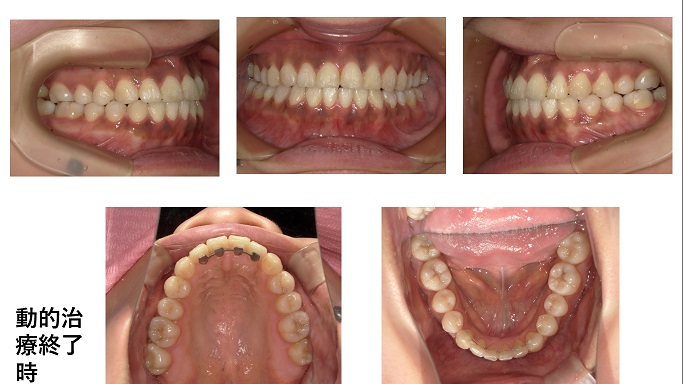

今回の症例は動的治療終了時の口腔内写真を見ると非抜歯症例と誤解を受けそうな写真です。

この患者さんは虫歯の治療を受けに当院を受診したところ下顎左側6番と上顎右側7番が虫歯が大きいので抜歯となりました。そこでこちらとしても欠損をどうするか考え、矯正を勧めました。欠損をそのままインプラントで補綴する選択肢もありましたが、矯正かインプラント又はブリッジと3つの選択肢を説明したところ2つ返事で歯列矯正をすることとなりました。

この症例の様に8番を7番に見立てる場合がありますので、使える8番は残せるなら残した方が良いです。歯医者によっては抜かなくてよい8番でも見つけたらすぐ抜歯する変な歯医者がいます。そんなところに通わなくてよかったです。